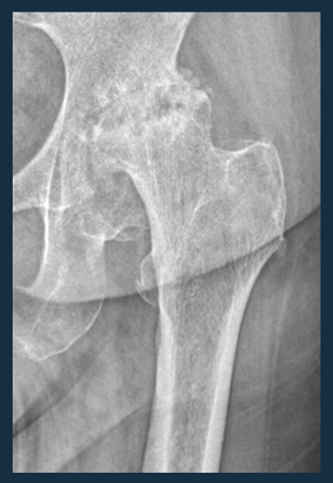

Koksartroz kalça eklemindeki kıkırdakların zamanla aşınması ve hasar görmesi durumudur. Koksartroz genellikle ağrı, sertlik, eklemde kısıtlılık ve hareket zorluğu gibi belirtilerle kendini gösterir.

3. Tanı: Koksartroz genellikle fizik muayene, röntgen, manyetik rezonans görüntüleme (MRG) gibi görüntüleme testleri ve hastanın semptomlarına dayalı değerlendirmelerle teşhis edilir.